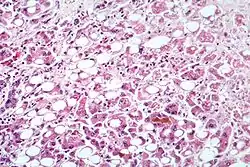

Hepatitis også kaldet leverbetændelse er en række sygdomme, der alle har betændelse i leveren som årsag. I daglig tale dækker hepatitis typisk over de smitsomme leverbetændelser forårsaget af en af følgende virussygdomme: Hepatitis A, Hepatitis B, C, D og E. Hepatitis dækker dog også over betændelse i leveren udløst af alkohol samt den ikke-alkoholiske fedtleverbetændelse, Non-alkoholisk steatohepatitis, der er forbundet med overvægt og Type-2 diabetes. Endvidere findes der flere autoimmune leversygdomme med leverbetændelse: Autoimmun hepatitis, Primær billiær kolangitis og Primær skleroserende kolangitis.